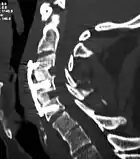

![]() X-rays of anterior cervical discectomy and fusion, C5C6 and C6C7. Lateral view. | |

Anterior cervical discectomy and fusion (ACDF) is a surgical procedure to treat nerve root or spinal cord compression by decompressing the spinal cord and nerve roots of the cervical spine with a discectomy, followed by inter-vertebral fusion to stabilize the corresponding vertebrae.[1] This procedure is used when other non-surgical treatments have failed.

The neurosurgeon or orthopedic surgeon enters the space between two discs through a small incision in front (= anterior) of and at the right or left side of the neck. The disc is completely removed, as well as arthritic bone spurs. The disc material, pressing on the spinal nerve or spinal cord, is then completely removed. The intervertebral foramen, the bone channel through which the spinal nerve runs, is then enlarged with a drill giving the nerve more room to exit the spinal canal.

To prevent the vertebrae from collapsing and to increase stability, the open space is often filled with a graft. That can be a bone graft, taken from the pelvis or cadaveric bone; or an artificial implant.[4] The slow process of the bone graft joining the vertebrae together is called "fusion". Sometimes a titanium plate is screwed on the vertebrae or screws are used between the vertebrae to increase stability during fusion, especially when there is more than one disc involved.